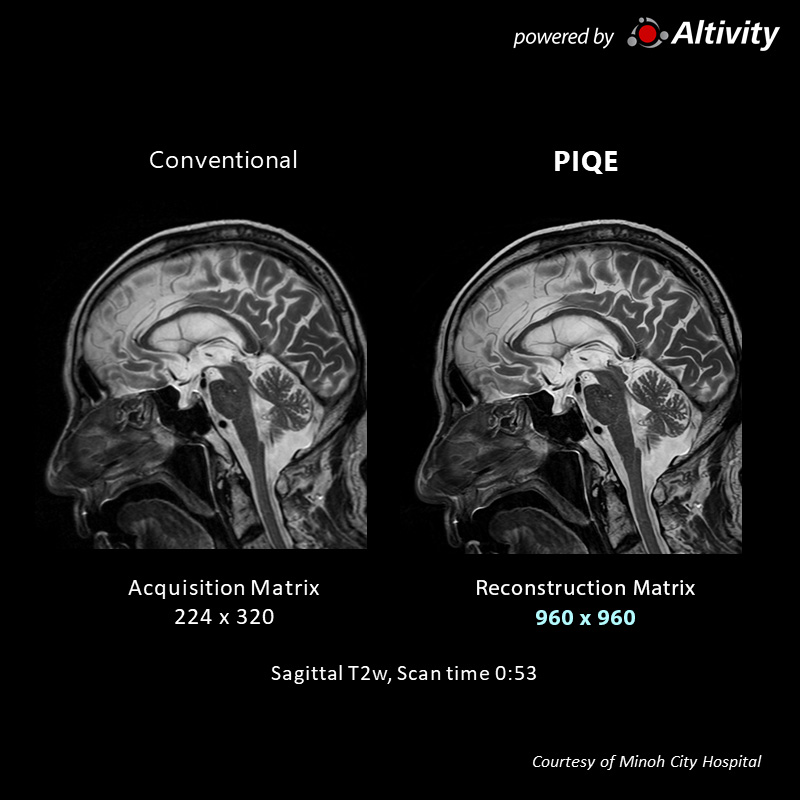

Sag T2w for pituitary

Using a regular head and neck coil, with a collection matrix 256 × 256 setting, imaging can be performed in approximately 1 minute. Structures around the pituitary gland are clearly visible.

Acquisition time: 1:08